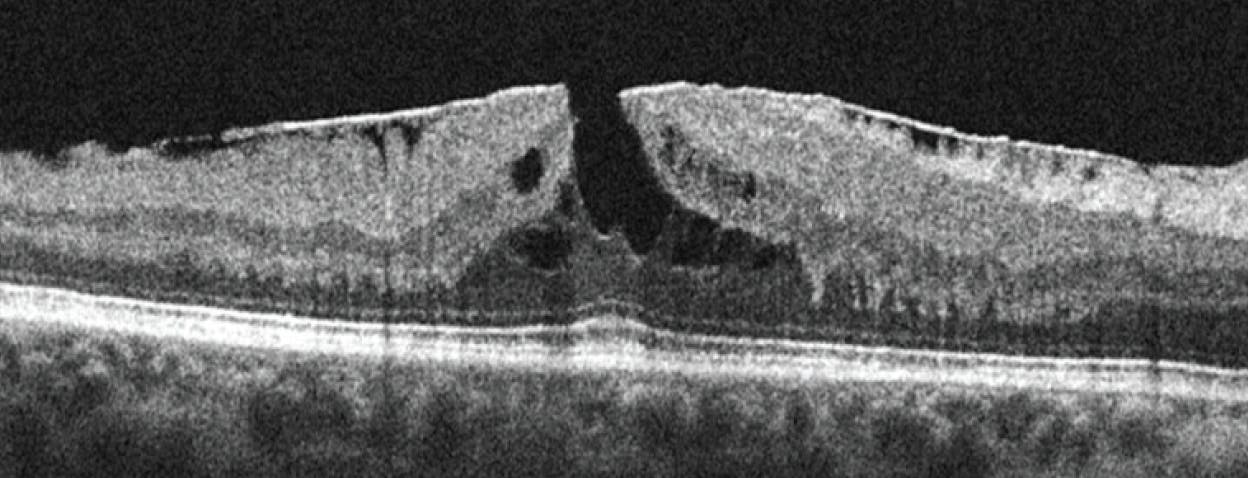

It is important to dynamically scroll through all OCT images on a particular patient with suspected macular hole, as oftentimes the abnormal foveal contour is not full thickness in nature. OCT makes it easier to identify partial-thickness holes, which are classified as lamellar holes or pseudoholes. Lamellar macular holes will exhibit an irregular foveal contour, a defect in the inner fovea, and intraretinal splitting while maintaining the integrity of the photoreceptor line. A lamellar hole can be described as tractional or degenerative, both of which have distinct characteristics. A tractional lamellar hole will have an ERM, a foveoschisis, and will take on a mustache appearance (Figure 6). A degenerative lamellar hole has an irregular foveal contour, foveal cavitation with round edges, loss of foveal tissue, round edges, and may exhibit epiretinal proliferation, which can be seen on OCT as a dense, homogenous tissue superficial to the ILM. Macular pseudoholes are also partial-thickness holes with heaped foveal edges, concomitant ERM with central opening, no loss of retinal tissue (Figure 7).13